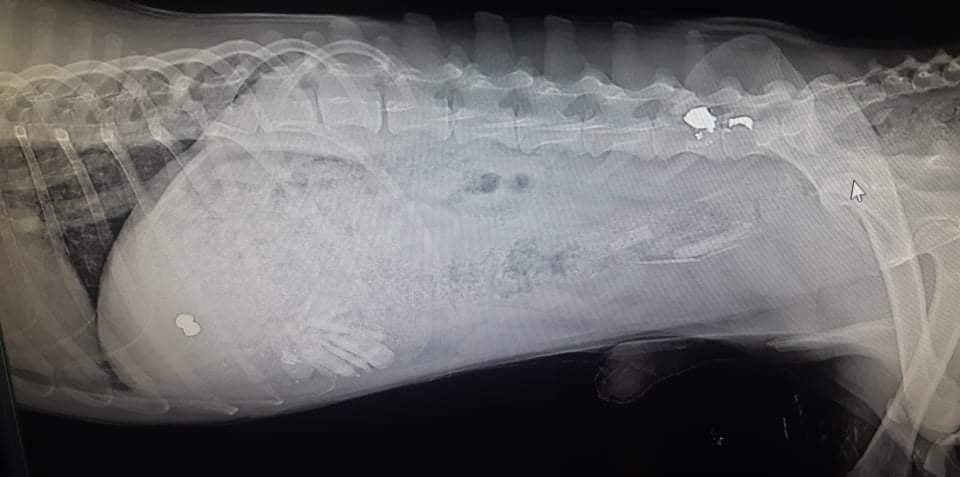

Според локални в селото Боби е бил блъснат, само че при рентгенови фотоси се оказа, че е било стреляно по животинката. По думите им кучето си имало собственик, само че той го изоставил, след претърпените от животинчето несгоди.

Ветеринарите установяват, че поради стрелбата и сачмите, заседнали в гръбнака му, Боби е неподвижен на половина. На втория ден след приемане в клиниката кученцето стопира да се храни и след тест се оказва, че е позитивно за парвовироза. В момента е на лекуване в клиниката, предстоят интервенции и лекуване.